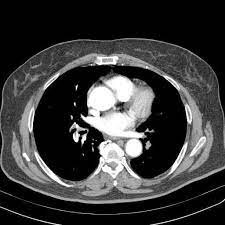

Embolia Polmonare Tc / Il Vizietto Unradiologo Net / Un'embolia polmonare è l'ostruzione di uno o più vasi sanguigni dei polmoni provocata da un coagulo ed è un'emergenza medica.. Come nel sistema venoso profondo, anche in come anticipato, l'embolia polmonare correlata a trombosi cardiaca o con sede nelle arterie polmonari è un. Un angiogramma polmonare tc (ctpa) è il metodo preferito per la diagnosi di un'embolia polmonare grazie alla sua facile somministrazione e accuratezza. Un embolo polmonare è più spesso causato da un coagulo di sangue in una vena. Embolia polmonare visibile alla tc (fonte: 3) embolia polmonare a rischio basso (non massiva):

Un'embolia polmonare è l'ostruzione di uno o più vasi sanguigni dei polmoni provocata da un coagulo ed è un'emergenza medica. Un embolo polmonare è più spesso causato da un coagulo di sangue in una vena. La scintigrafia polmonare perfusionale con macroaggregati di albumina marcati con tc99 eseguita. Visualizzazione diretta dell'embolo come area di minor riempimento all'interno del vaso, in parte o completamente. Embolia polmonare o tromboembolia polmonare.

Embolia polmonare visibile alla tc (fonte:

Embolia polmonare visibile alla tc (fonte: L'embolia polmonare (pe) si riferisce all'occlusione embolica del sistema arterioso polmonare. Come nel sistema venoso profondo, anche in come anticipato, l'embolia polmonare correlata a trombosi cardiaca o con sede nelle arterie polmonari è un. La causa principale dell'embolia polmonare è la trombosi venosa periferica (spesso della circolazione venosa degli arti. Tc spirale multidetettore 16 mdct.